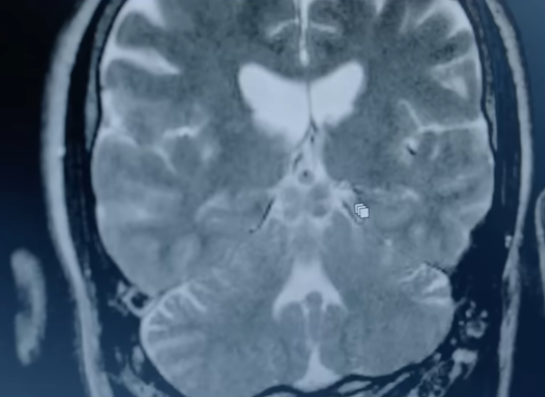

Human consciousness: from fetal to neonatal life

The beginning of human personhood is the moment when a human is first recognized as a person. There are differences of opinion as to the precise time when human personhood begins and the nature of that status. The issue arises in a number of fields including science, religion, philosophy, and law, and is most acute in debates relating to abortion, stem cell research, reproductive rights, and fetal rights. The fetus may be aware of the body, for example by perceiving pain. It reacts to touch, ...

National Science Foundation research shows babies begin to acquire knowledge in the womb

A Dutch study found that by 30 weeks of age a fetus can remember a sound for 10 minutes. By week 34, a fetus may be able to remember. During rapid-eye-movement sleep, when we dream, the brain is thought to be processing stored memory. The memory of a newborn infant is dominated by its fetal experience, and the infant is likely to dream about its life in the womb. Research with lucid (or conscious) dreaming has shown that dream images are supported by the corresponding body actions, using thos...